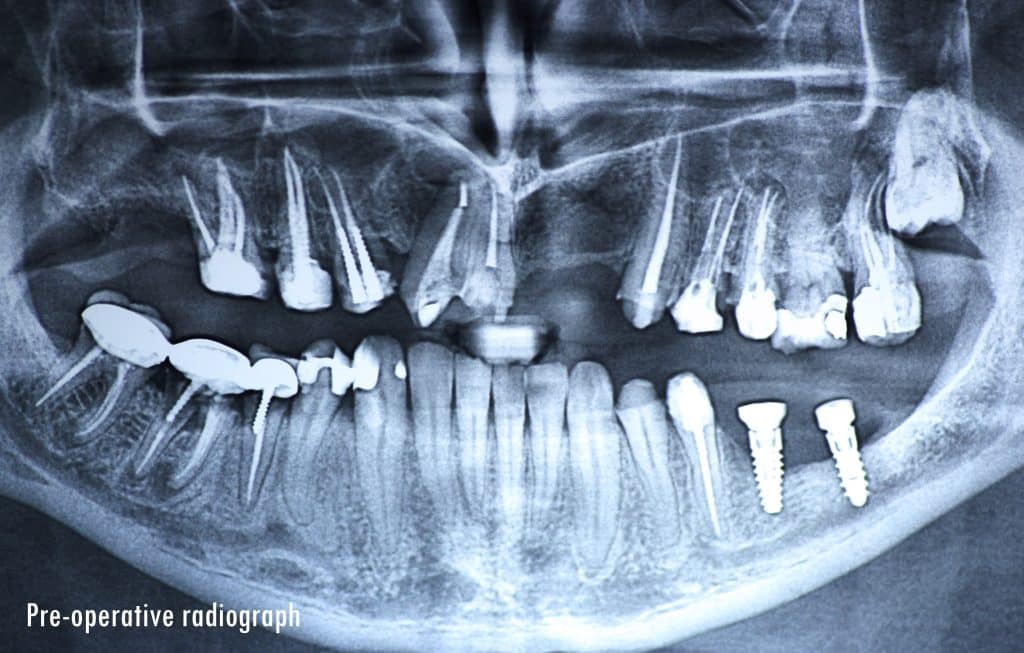

35 years old male patient having old PFM restorations

The patient was normally class I occlusion type ( according to old photos and cephalometric analysis) till he received this defective restorations 10 years ago

The patient was diagnosed by orthodontist, oral surgeon and prosthodontist to make the best treatment plan

1- Removal of old restorations

2- Restorative phase ( including RCT, post and core )

9- Fabrication of RPD posteriorly till implant phase

10- The next phase will be implants in the posterior region